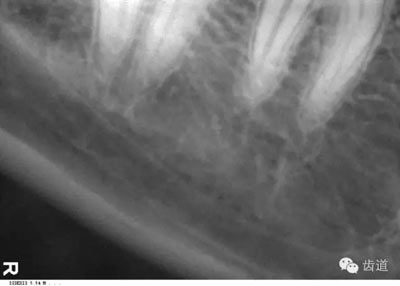

6)下頜骨下緣:

膠片在口內(nèi)放的位置過低,在牙根尖下方X線片上顯示為帶狀密度很高的影像。